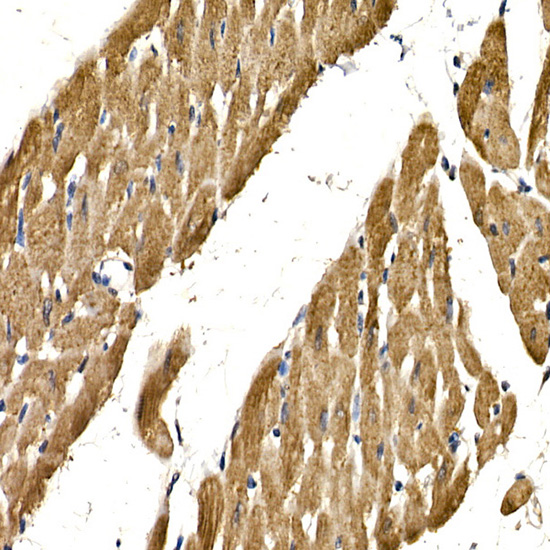

Immunohistochemistry of paraffin-embedded rat heart using PDGFB Rabbit pAb.